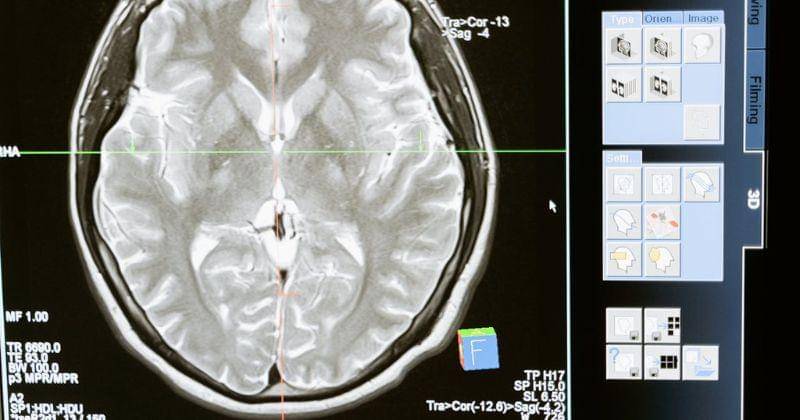

Sementara itu untuk diagnosis sendiri untuk penyakit ini yakni melalui tes neurologis untuk mengidentifikasi area otak yang terpengaruh. Lalu, ada tes bahasa yang menilai kemampuan berbicara, memahami, membaca, dan menulis hingga pencitraan otak melalui MRI atau CT scan membantu mengidentifikasi lokasi kerusakan.